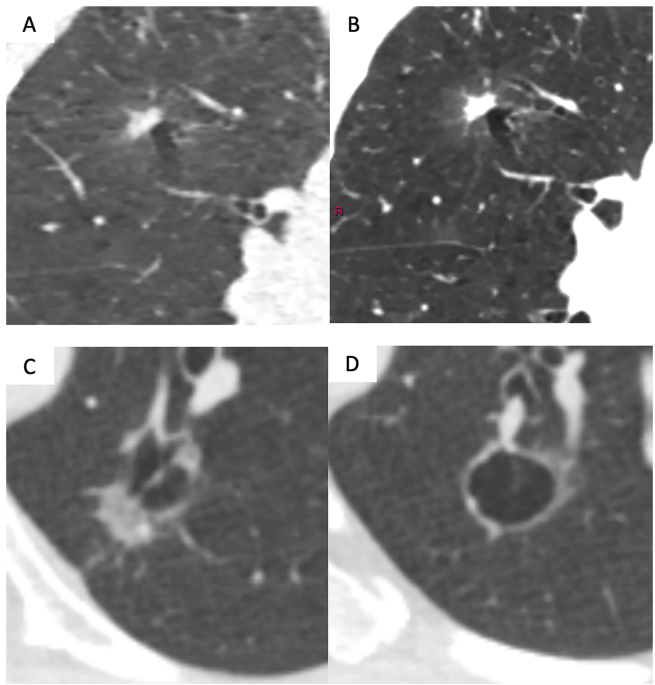

这篇综述由欧洲胸科影像学会(ESTI)制定,聚焦低剂量CT(LDCT)肺癌筛查中的结节管理策略。通过整合国际指南(如Lung-RADS v2022、NELSON等),提出以结节侵袭性(aggressiveness)为核心的风险分层方案,强调体积测量(volumetry)和形态学特征(如毛刺征、胸膜凹陷)的联合应用,旨在减少过度诊疗(overtreatment)和阶段迁移(stage shift),同时优化随访流程。文中还探讨了人工智能(AI)和深度学习在风险预测中的潜力。

肺癌是全球癌症死亡的首要原因,早期诊断对提高生存率至关重要。低剂量CT(LDCT)筛查在高风险人群中可显著降低肺癌特异性死亡率,但结节管理的标准化仍是挑战。欧洲胸科影像学会(ESTI)基于现有指南(如Lung-RADS、NELSON)提出新建议,核心是通过评估结节侵袭性优化随访策略。